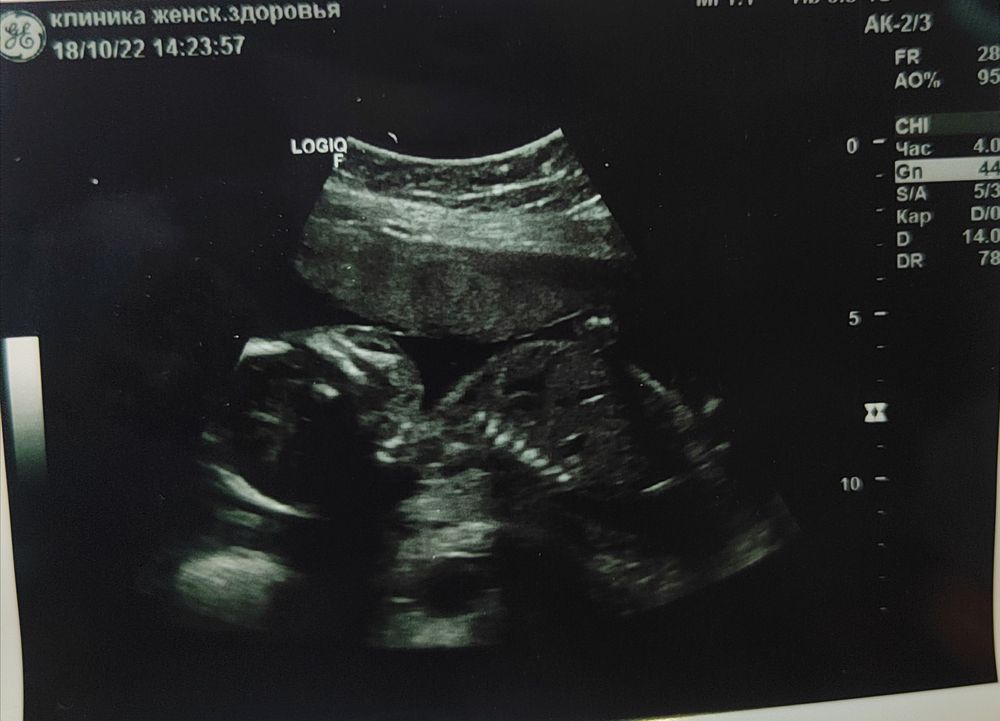

2 скрининг

Какая красота! Поздравляю вас с сынишкой с новой встречей 😊 Так же хорошо и дальше доходить 💪